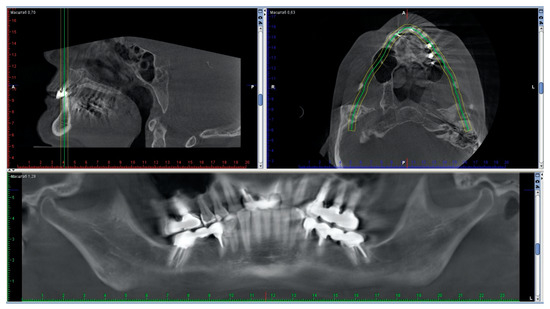

A second CBCT recorded while wearing the splint verified the match between virtually-planned and the actually-obtained mandibular positioning. The intra-articular space widths wearing the splint confirmed the achievement of the desired condylar position and the normalization of the values (Figure 8 and Figure 9). These results seem to validate the precision of this full digital workflow.

Figure 9. Normalization of the values of the intra-articular space widths assessed by the repeated CBCT, taken with a splint in the oral cavity.